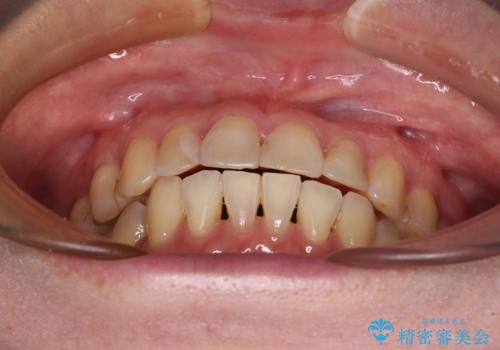

- 前歯のデコボコを気にして来院された患者様です。

舌突出癖により、上下前歯がなかなか接触せずに治療期間を要しましたが、舌のトレーニングにより無事に治療を終えることができました。